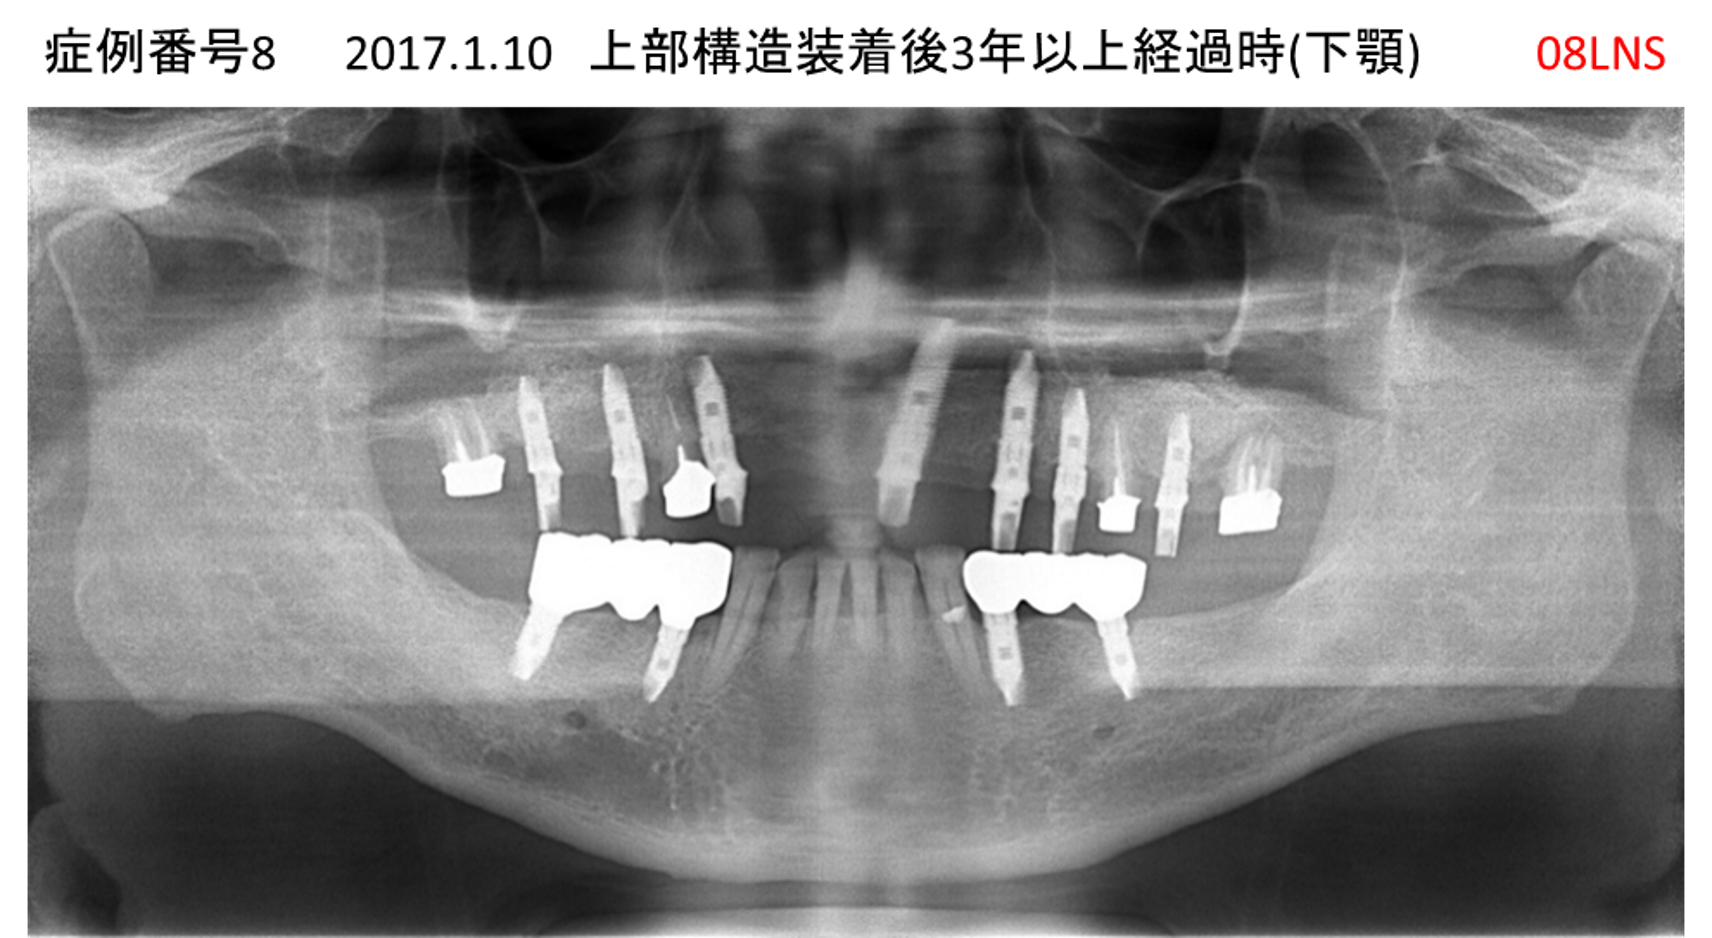

全く噛めない患者様のインプラント症例

| 治療名称 |

インプラントAGC |

| 治療費用 |

860万円+税 |

| 治療期間 |

12か月 |

| 患者さんの症状(主訴) |

全く噛めない、ごはんが後もに食べられるようになりたい、人前で口元を隠したくない |

| 治療内容 |

サイナスリフト、GBR、インプラント、AGC |

| 治療結果 |

しっかり噛めて踏ん張ることができる。食べ物をを選ばなくて済む、何でも食べられる、体重が増えた。見栄えがきれいすぎて自分じゃないみたい |

| 治療の注意点(リスク/副作用) |

インプラントが壊れたら再治療が必要 |